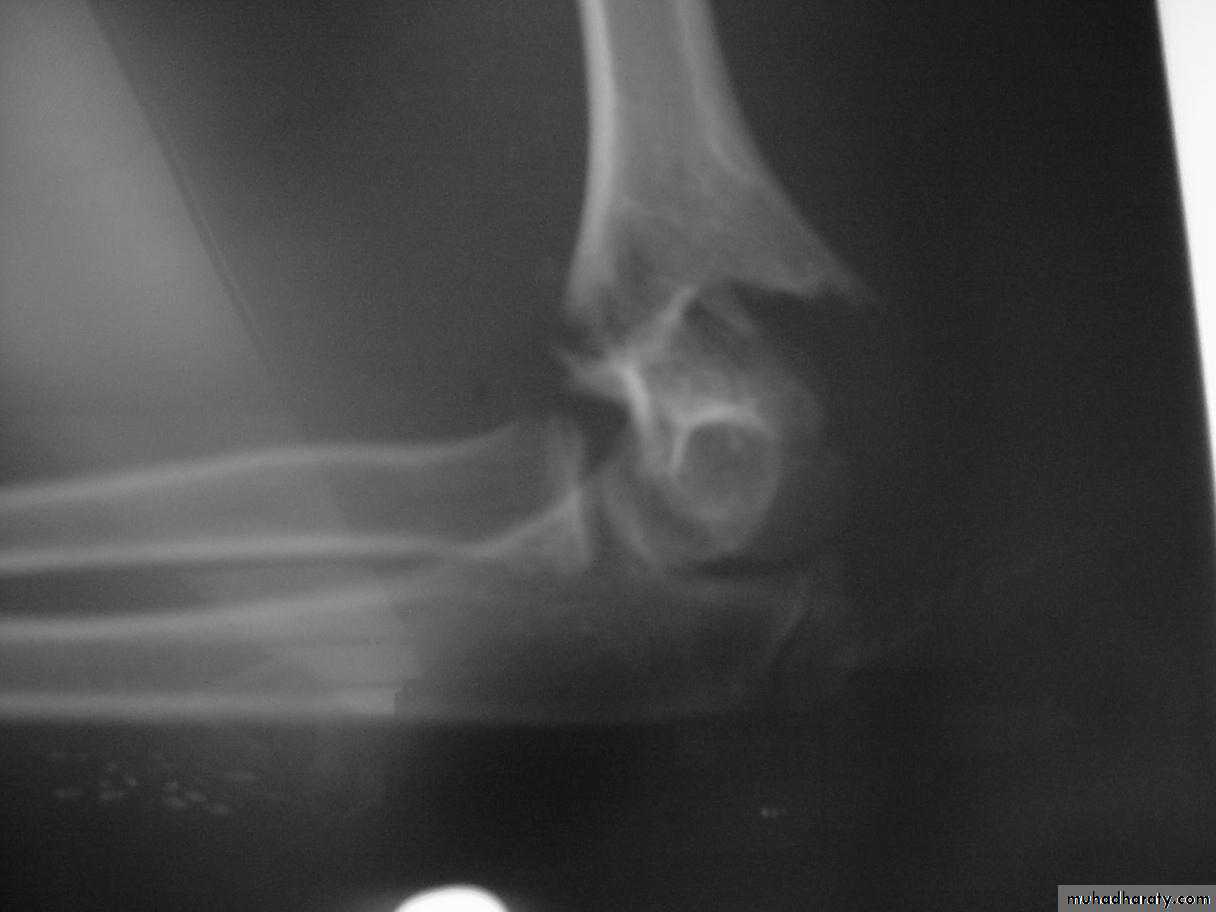

This fracture

was irreducibleby closed

manipulation.

Injury film

The posterior

tricepssplitting

approach

Advantages:

Easy approach

Direct

visualization

of fracture site

Disadvantages:

Injures virgin

tissue

Unable to

visualize

anterior A. & N.

*Compliments of Jamie Maclean(Pearth ,Scotland)

*What is the primary purpose of an open reduction?